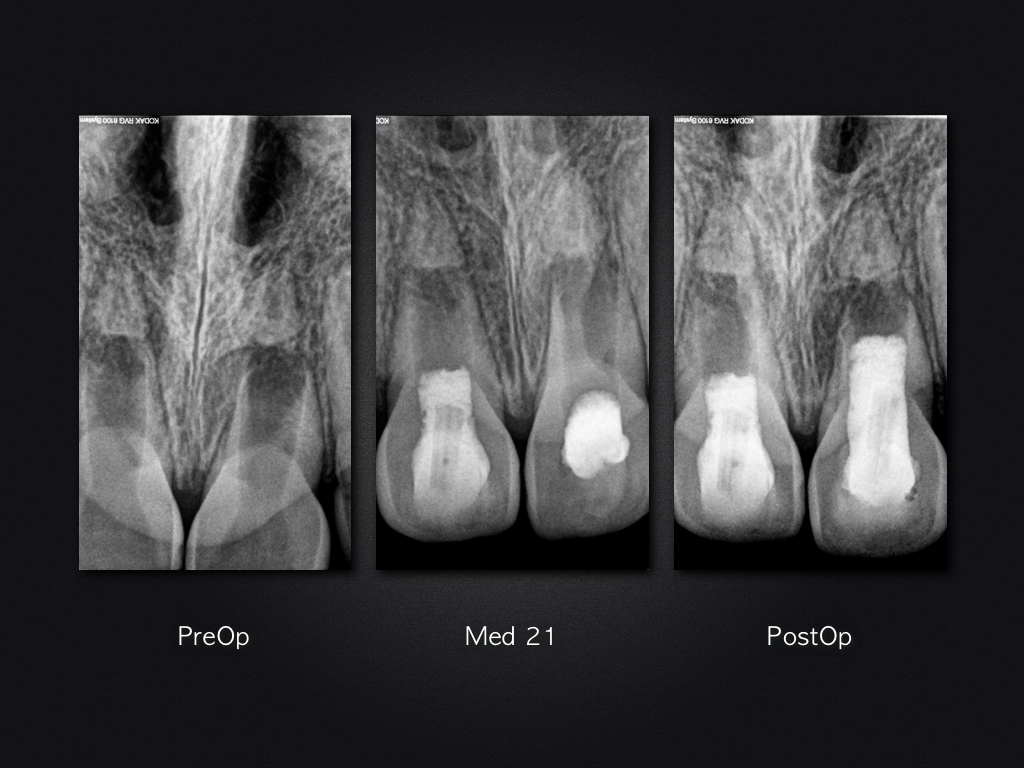

Letzte Ausfahrt Regeneration – Recall